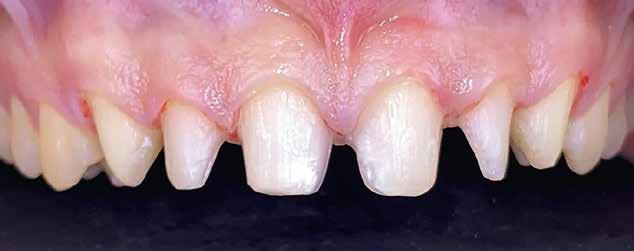

Interdiszciplináris fogászati kezelés myofunkcionális készülék, alignerek és protetikai ellátás alkalmazásával

MED. DENT Abradált frontfogakkal rendelkező felnőtt páciens interdiszciplináris kezelése